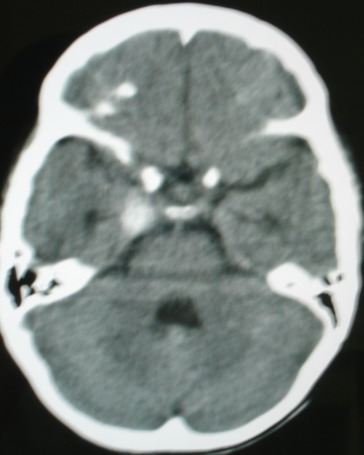

标题: PED0834:M8Y,考虑右侧海绵窦血管瘤 [打印本页]

标题: PED0834:M8Y,考虑右侧海绵窦血管瘤

m/8y,右侧眼睑下垂数天,头昏,无呕吐、无外伤史。无搏动性突眼。病人明天来增强。

考虑颈内动脉海绵窦段动脉瘤,建议mri检查。